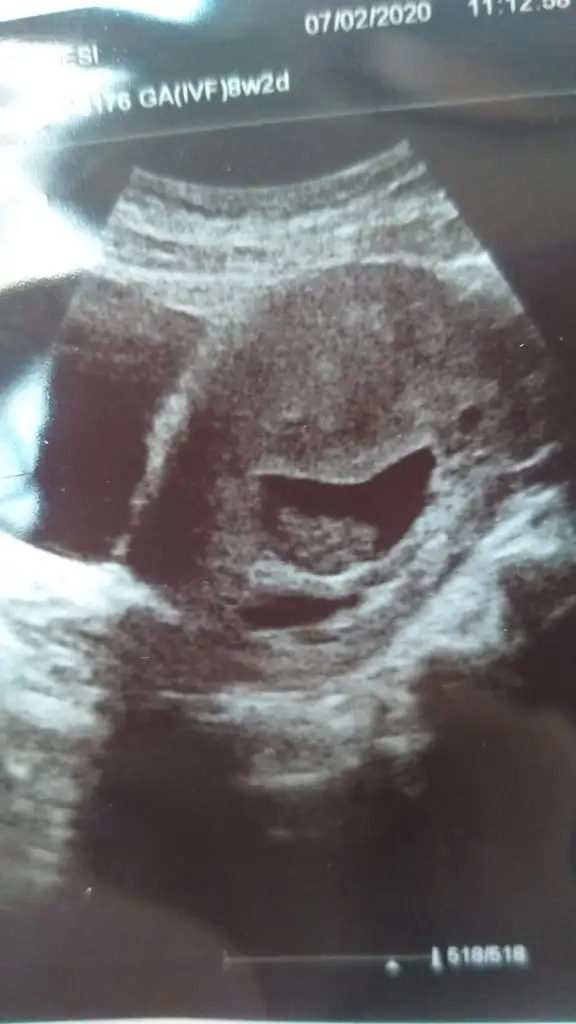

Albatros2 Albatros2 bu şekilde bide 9.Haftaya yeni girmiş gebeler sizinde mi ultrason görüntünüz boyleydi

Arkadaşlar lütfen 8 veya 9. Hafta başında olanlar ultrason görüntünüzü paylaşabilir misiniz içim hiç rahat değil